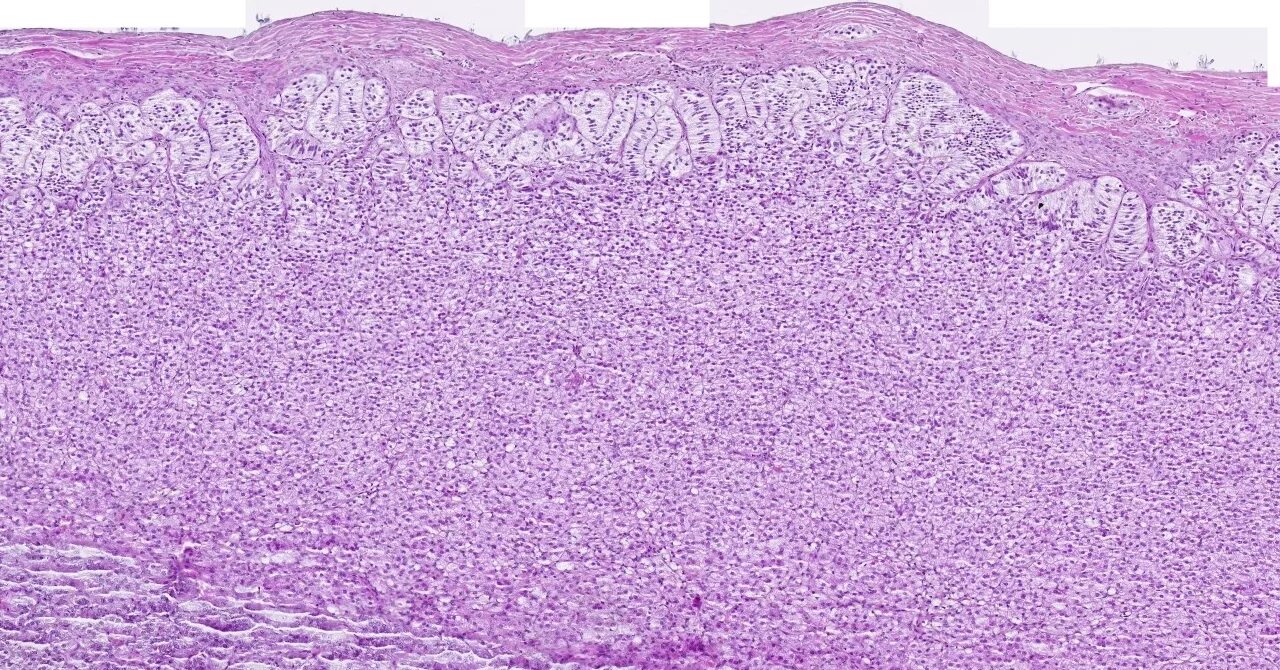

Гистология после